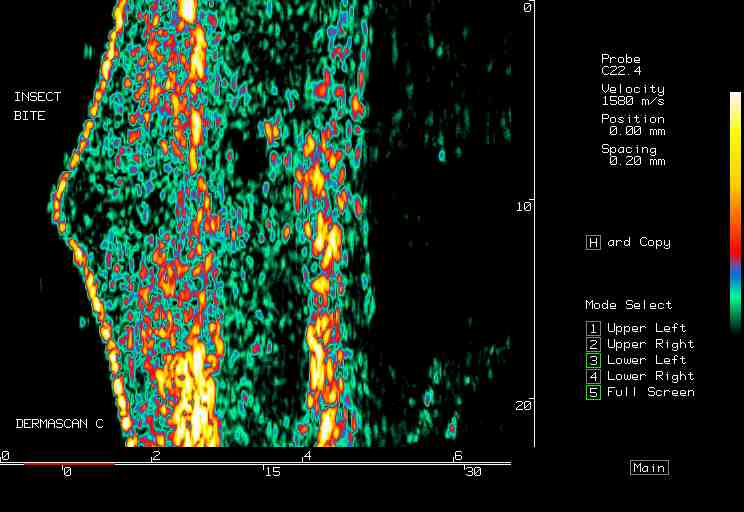

20 MHz 2D images

| Reactions |  Irritant reaction |

Insect bite |